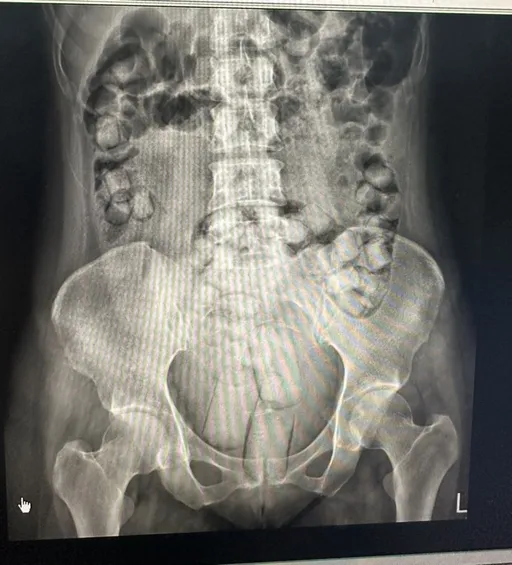

女騎士向警方表示,其夫早上突然感到腹部劇痛,她騎機車載丈夫趕往醫院就醫,但因丈夫疼痛難忍所以機車搖晃。警員見情況急迫,立即請女騎士把車停下,把2人帶上警車,開啟警示燈及蜂鳴器,在兼顧安全的情況下,護送他們火速趕往醫院。原本須7分鐘的路程,於3分鐘內趕到,迅速協助就醫。